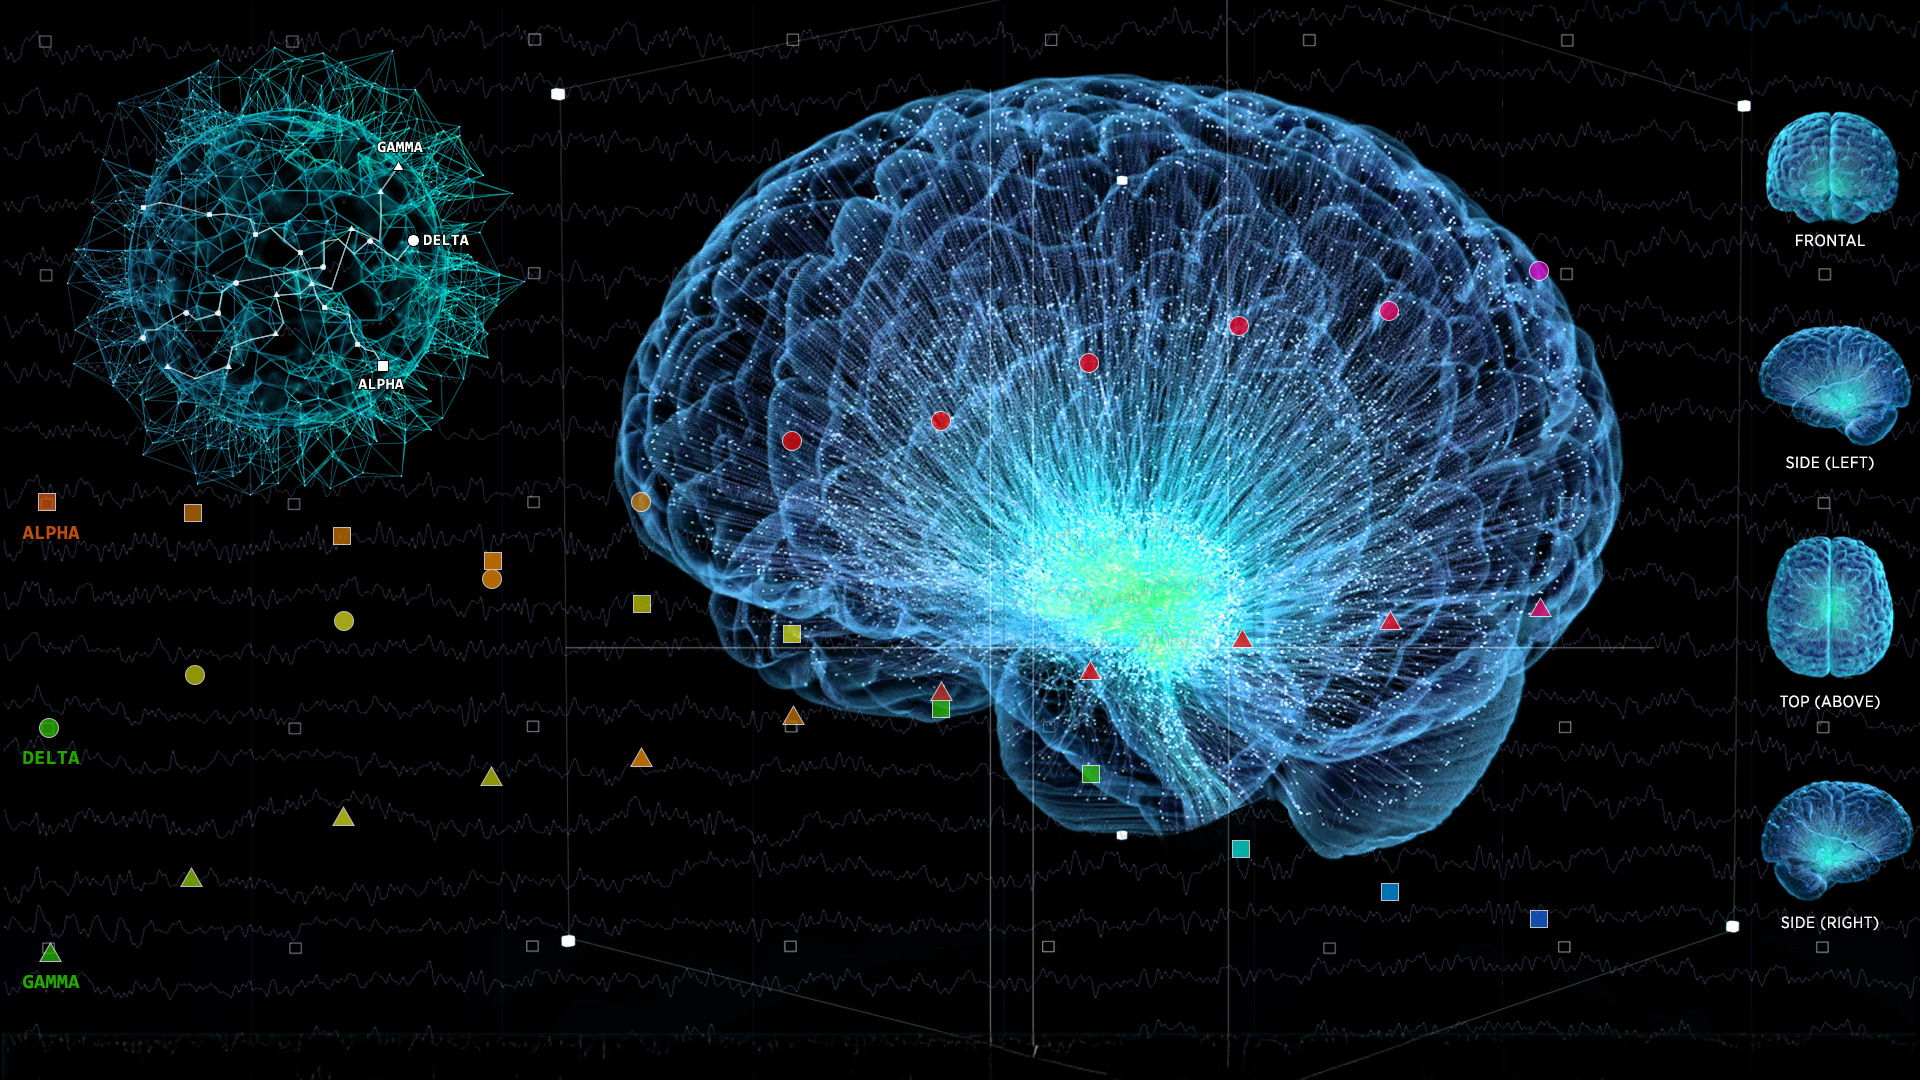

How Does It Work?

Proven 3-Step Process for Brain Performance Enhancement

We combine cutting-edge neuroscience and EEG scanning with practical, real-world applications to achieve measurable improvements in your brain’s performance. Through research-backed TTI assessment tools, we measure individuals’ behaviors, what motivates them, their emotional intelligence, and stress levels.